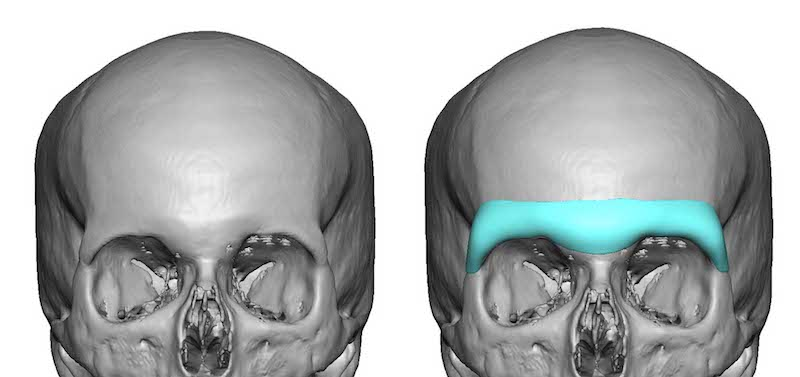

Supraorbital Implants

This procedure enhances the upper orbital rim, improving brow and forehead projection, and balancing facial contours.Overview

Incisions are made along the upper eyelid crease or hairline.Custom or preformed implants are placed above the orbital rim.

Implants are fixed with screws or sutures to maintain position.

Pros:

Restores upper orbital volume and brow supportImproves overall eye contour and reduces deep-set appearance

Can complement brow lifts or forehead rejuvenation

Cons:

Risk of visible implant edges if not properly placedSwelling, bruising, and temporary numbness may occur

Longer recovery compared with non-implant procedures

Price: €3,500–€12,000